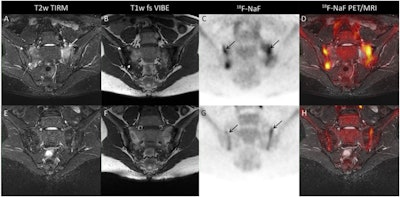

Atherosclerotic inflammation captured by F-18 FDG-PET/MRI. Image courtesy of Seminars in Nuclear Medicine.PET technology has improved significantly in recent years, and hybrid PET/MRI scanners are now offering increased axial field of views that result in higher sensitivity. But more must be done to understand the technology's benefits. Sollini's team sought to do just that via a literature review that included 65 articles gleaned from PubMed from January 2018 to July 2022.

- The team observed an increasing trend in bone and joint publications (12 of 65) over the course of the study's time frame.